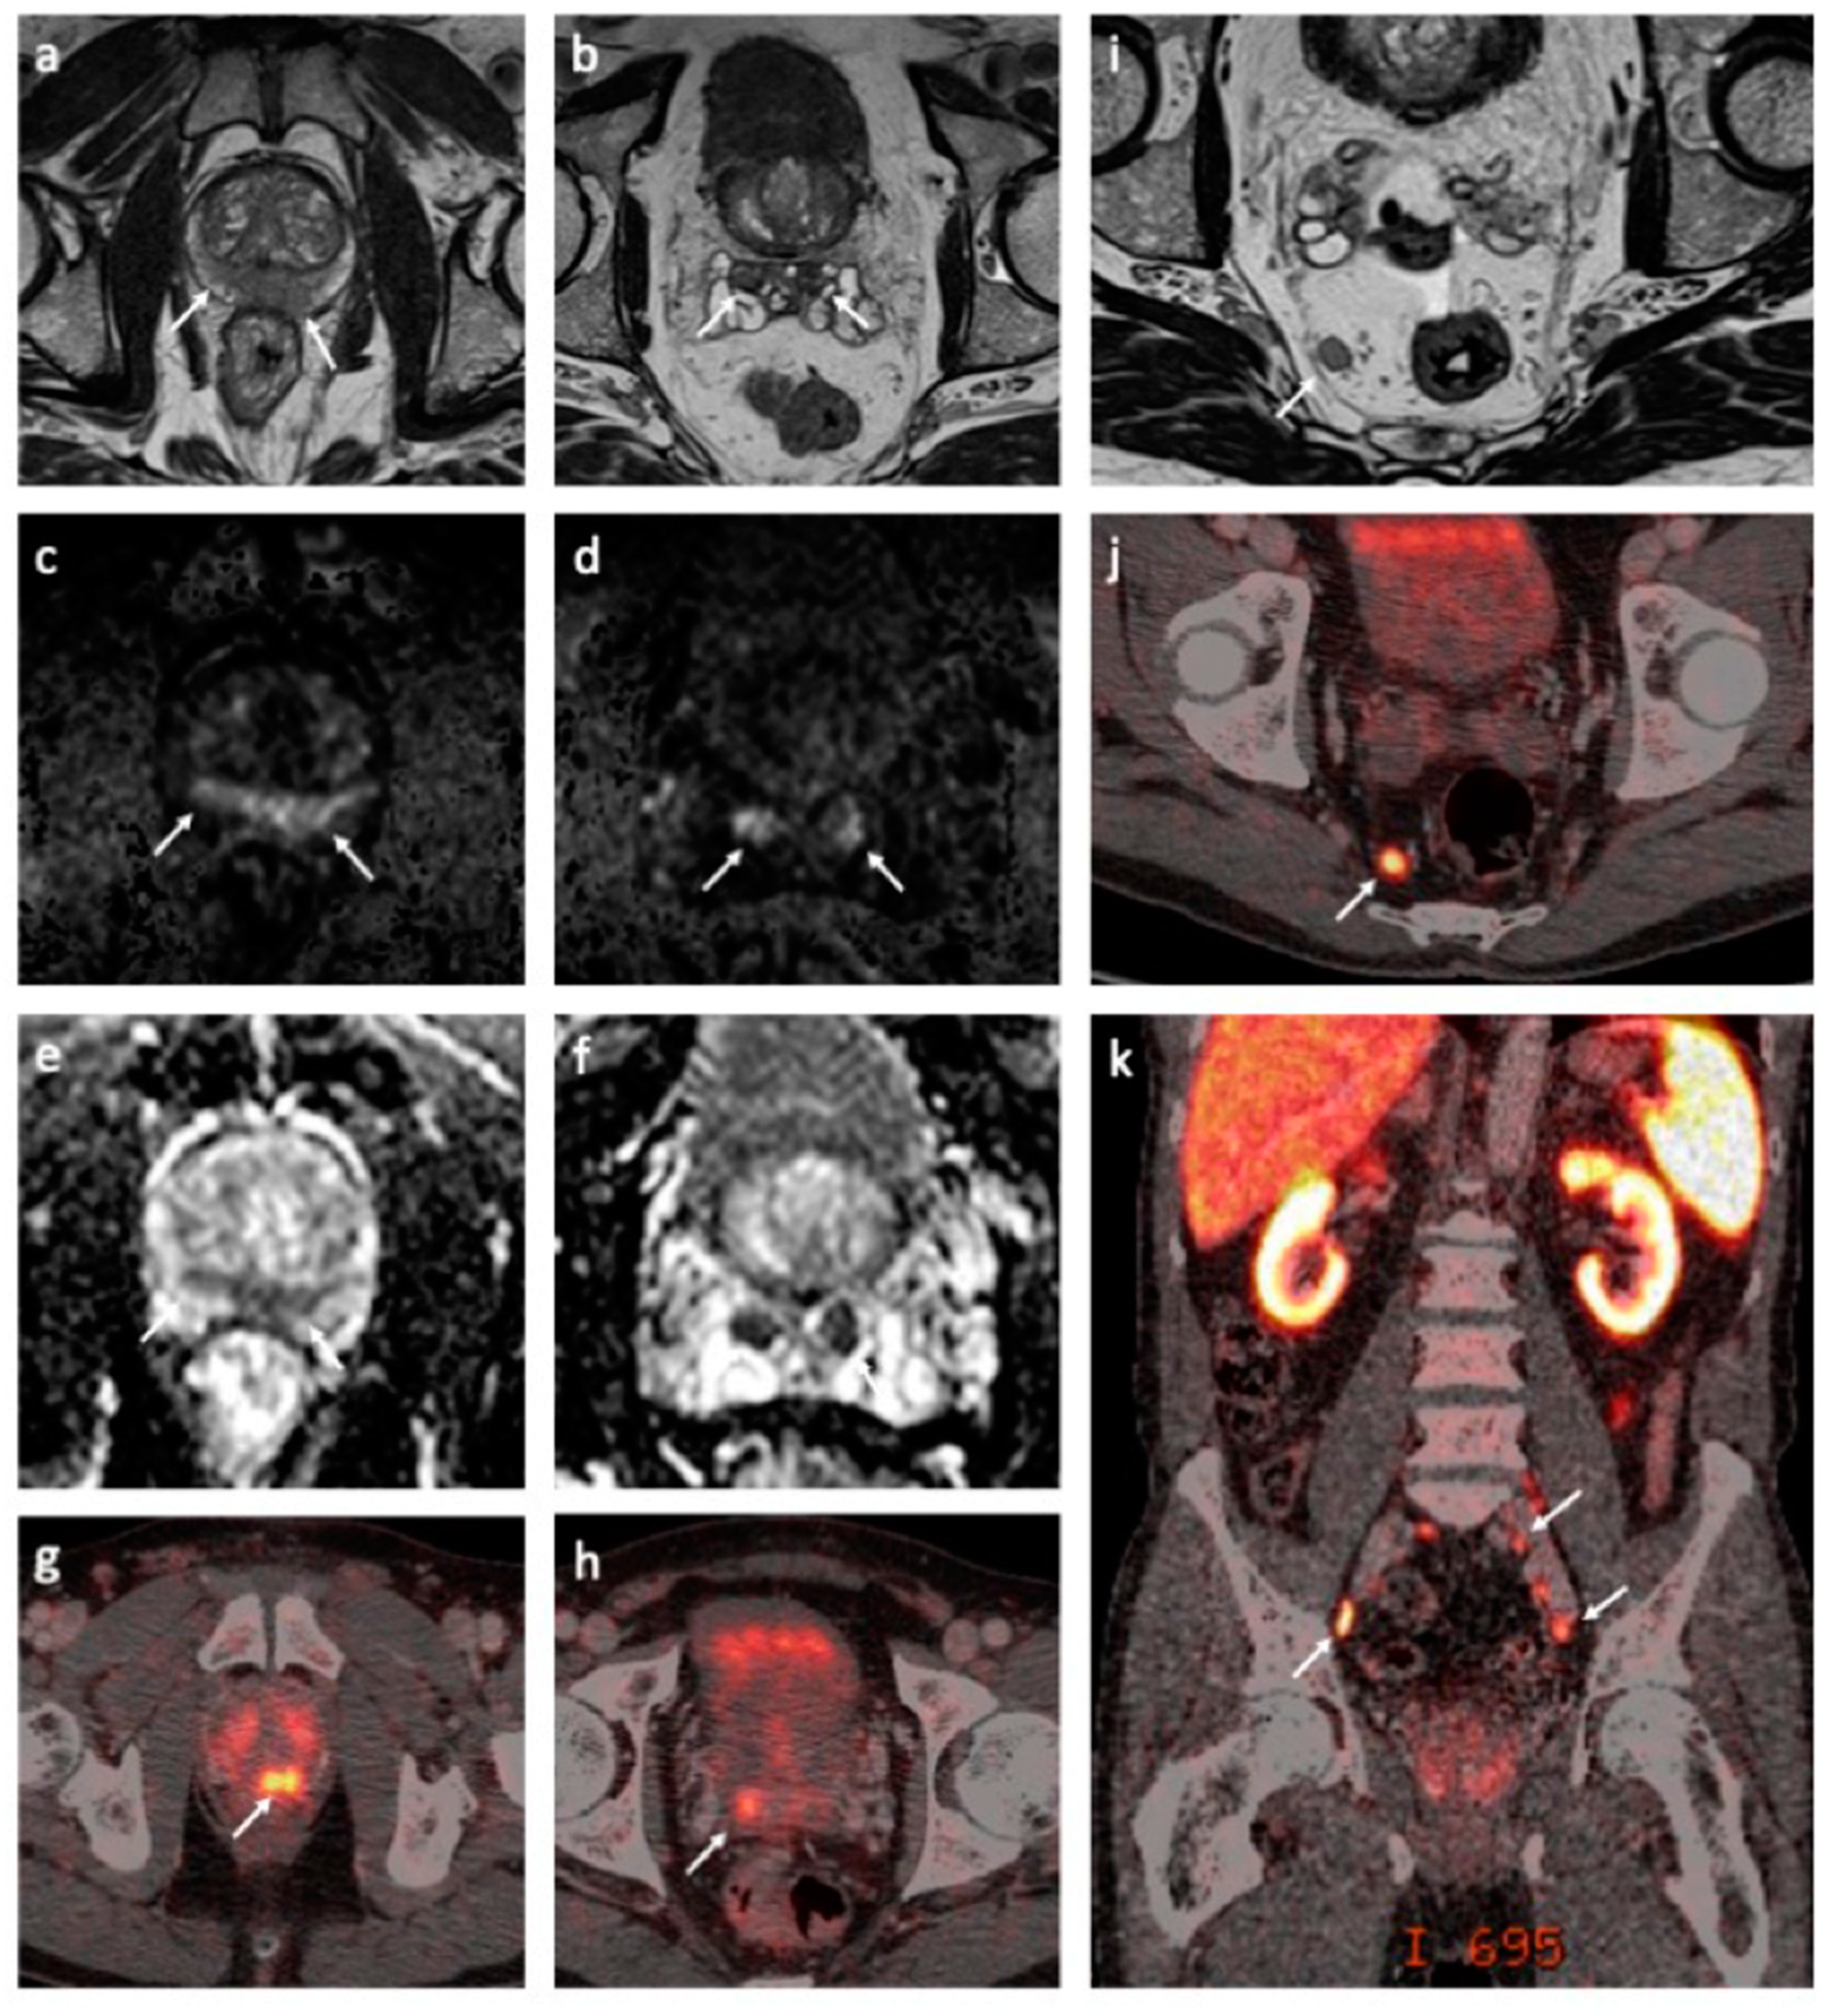

Before the initiation of long-term ADT, new snap-frozen biopsies were sampled, stored in nitrogen, and sent for whole-exome and transcriptome sequencing. The obtained results were discussed within a tumor board. A combined treatment with ADT and radiotherapy was suggested. After four months of ADT, the total testosterone suppression was achieved by adding enzalutamide to goserelin during and after radiation. Due to COVID-19-related delays in the course of treatment, fiducial gold markers were installed in the prostate in late-April 2020, and image-guided conformal radiotherapy of 74 Gy to the prostate was applied from May to June 2020. The patient had a PSA nadir of 0.44 ng/mL at the end of the radiotherapy, and he was subsequently followed by his local oncologist. A follow-up MRI scan revealed signal changes on fat-only and water-only Dixon images and diffusion-weighted images (DWI) within the suspected lesion in the thoracic spine, presumably consistent with the treatment response of the bone marrow metastasis (Figure 2). Furthermore, a correspondingly good treatment response in baseline radiographically outlined lesions was revealed in the prostate tumor and lymph node metastases on follow-up MRI.

Figure 2. The left panel (a,b) shows pretreatment magnetic resonance imaging (MRI) and computed tomography (CT) scans of the thoracolumbar spine. Small, focal lesion in the thoracic spine is shown on MR ((a), white arrow) and CT ((b), white arrow) images. The right panel (ce) shows follow-up MRI and CT performed after the start of combined androgen deprivation therapy. A sagittal T2-weighted fat-only Dixon image demonstrates an increased fat signal within the suspected lesion in the thoracic spine (c, white arrow). There was no evidence of tumor activity on the diffusion-weighted MRI (DW-MRI) (d). CT of the thoracolumbar spine showed subtle perilesional sclerosis ((e), white arrow). The findings (ce) have appeared since the pretreatment MRI and CT scans and are presumably consistent with the treatment effect in solitary bone marrow metastasis.